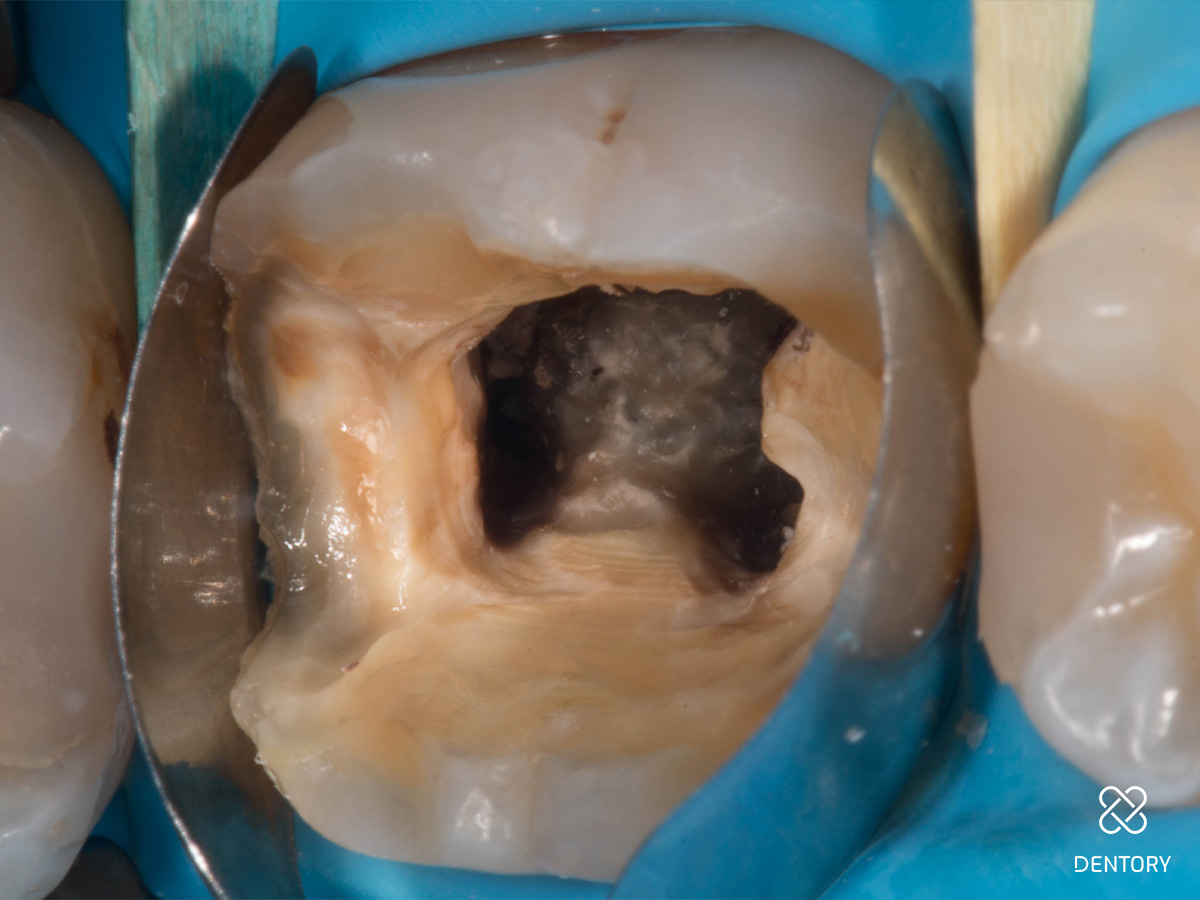

Abbildung 2

Entfernung der insuffizienten Füllung. Man kann erkennen, dass die Guttapercha aufgrund der hohen Transluzenz des damals verwendeten Materials durch die Füllung scheint.